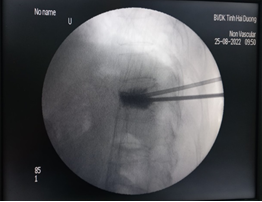

Bước 5: Đây là bước quan trọng nhất khi thực hiện kỹ thuật, xi măng sinh học sẽ được bơm qua kim định vị rỗng rỗng vào thân đốt sống bị xẹp. Tốc độ bơm phải chậm và được theo dõi chặt chẽ của bác sĩ thông qua C-arm và những biểu hiện lâm sàng của bệnh nhân như tình trạng đau hay cử động hai chân.

Bước 6: Để chắc chắn xi măng sinh học chỉ khu trú trong thân đốt sống, bác sĩ sẽ kiểm tra bằng C-arm hai bình diện thêm một lần nữa.

Sau khi thực hiện xong kỹ thuật, bác sĩ sẽ đánh giá toàn bộ quá trình thực hiện. Kỹ thuật thành công khi xi măng lan tỏa trong thân đốt sống bị xẹp, không có tình trạng thoát xi măng ra bên ngoài đốt sống. Sau khoảng 4-5 giờ xi măng đông cứng hoàn toàn, người bệnh có thể đi lại bình thường và tình trạng đau đốt sống được cải thiện rõ ràng.